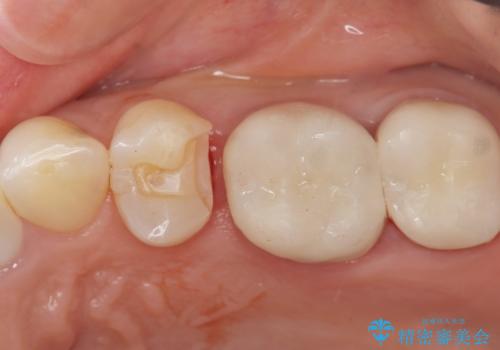

銀のつめものを除去したところ、大きなう蝕を認めました。

咬合力が強いため、割れる心配がなく強度の高いPGA(ゴールド)インレーをご希望されました。